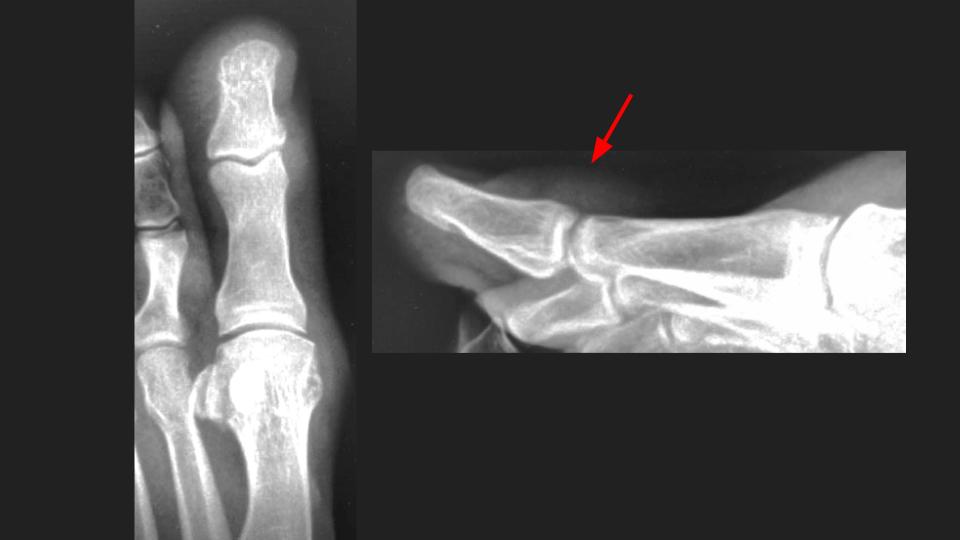

Aspirated and proven Gout of the first toe interphalangeal joint.

There is an intermediate T1 / Bright PDFS, STIR signal mass dorsal to the hallux IP with subtle erosion (arrow in short axis MRI) and no BME. No joint space narrowing, mild IPJ synovitis (not shown). XRs and US send as screenshots from referrer. She aspirated whitish greenish material from the dorsal IPJ mass/collection.